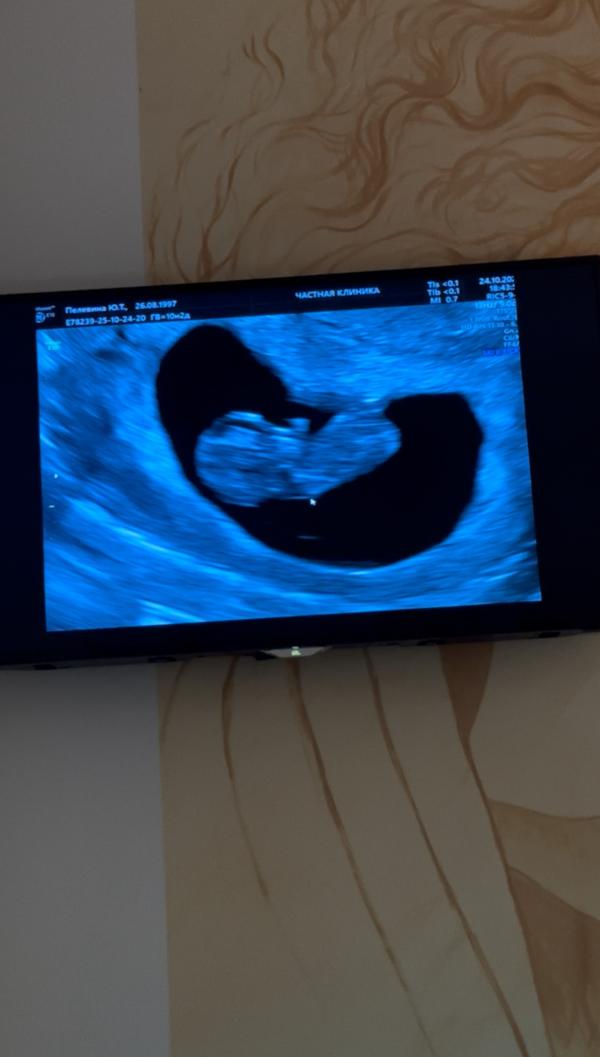

10.3 по месячным ❤️

КТР - 27 мм

соответствует сроку 9.4 из-за поздней овуляции 😌

Ходили с мужем. Послушали сердечко, посмотрели, как малыш двигает ручками и ножками. Все хорошо 💕